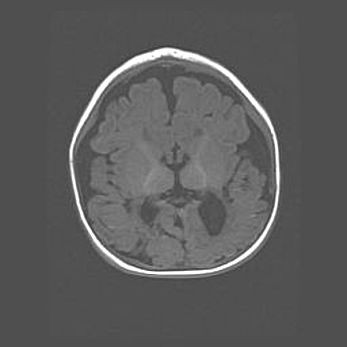

Церебральная ишемия II.

Возраст: 5 дней

Вес: 3400 г

Пол: женский

Окружность головы: 35 см

Срок гестации: 39 недель

Церебральная ишемия – это заболевание, характеризующееся недостаточностью (гипоксией) либо полным прекращением (аноксией) снабжения мозга кислородом по причине закупорки одного или нескольких сосудов. Это приводит к  что метаболическим расстройствам различной степени тяжести в тканях головного мозга, развитию коагуляционных некрозов и гибели нейронов.